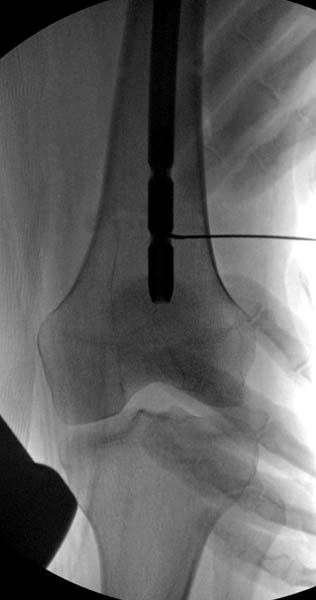

Остеосинтез бедра не стали делать из-за множественных переломов ребер с ушибом грудной клетки и поэтом у закончили фиксацию бедра наружным фиксатором.

Около 11.00 вечера больная переведена в реанимацию, без сознания, но стабильная.. На третьий день провели стабилизацию перелома бедра антеградным остеосинтезом.

Закрытый БИОС решает множественные проблемы связанные с лечением переломов, но проблема дистальной блокировки без рентгена до сих пор остается нерешенной. Рекламированные производителями приспособления для дистальной блокировки из-за различной кривизны кости не эффективны или стоит очень дорого (Smith&Nephew SureLock). Задержка операции из-за блокировки не всегда удовлетворяет, и многих вынуждает искать альтернативные методы фиксации. С результатами таких действий, остеомиелитом и несращениями, встречаемся в ежедневной жизни..

Для решения проблемы дистальной блокировки компания DigiMed недавно предложила систему блокировки без рентгена. Пока в стране только два набора и только для антеградных гвоздей, но компания работает над созданием устроиства для других гвоздей тоже..

Результат первых случаев показала отсутствие разницы между занятиями на муляжах, а также Workshop и с удивительной точностью вывел латерально над кожей специальное сверло. Дальше по сверлу тонкий направитель и проводится сверление каннюлированным сверлом....